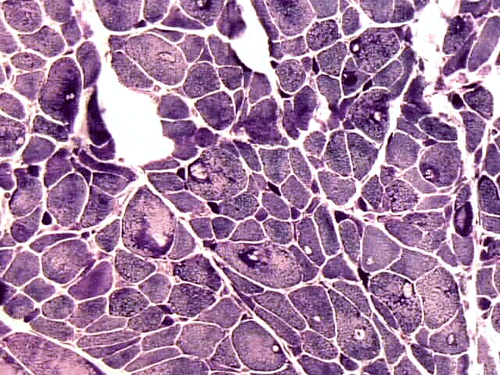

On hematoxylin-eosin stained sections, there is an increased variation of fiber diameter with many atrophic fibers intermingled with fibers of normal caliber. There is no evidence of fiber grouping or perifascicular atrophy. No inflammatory cells are present. There is also mild interstitial fibrosis (Panel A). On higher magnification, many fibers have a round concentric structure (Panel B). Irregular, centrally located depositions are also identified on modified Gomori's trichrome. The concentric nature, however, is not as obvious as in the hematoxin-eosin stained sections (Panel C). Type I and II fibers are not clearly separated in the ATPase preparation at pH 9.4. This is a common situation in chronically ill muscle (Panel D). The type I fibers are unusually dark. There is an increase in the proportion of type I fibers. The atrophic fibers are usually type II fibers. The concentric lesions are found predominantly in type I fibers (Panel E). There is an increase in PAS staining which is consistent with increased glycogen storage (Panel F). No increase in lipid content is demonstrated by oil red O (Panel G). On NADH-TR reaction, the concentric structures appear to have a clear central core that is devoid of enzymatic activity, a rim with intense enzymatic activity and a surround zone with relatively normal reactivity. These features are classic for target fibers (Panel H and I). No deficiency of laminin-2 (merosin) (Panel J) or dystrophin (Panel K) is demonstrated by immunohistochemistry. The central lesions are also immunoreactive for both laminin-2 and dystrophin. Immunohistochemistry for desmin demonstrate a core of strong immunoreactivity and also strong reaction in the sarcoplasmic membrane (Panel L and M). The target structures are also well demonstrated on semithin sections (Panel N). On electron microscopy, z-disc streaming is a common finding and they are often admixed with a substantial amount of dense granular electron dense substance (Panel O and P). There are also numerous cytoplasmic bodies characterized by radiating intermediate filaments (spheroid bodies) (Panel Q and R).